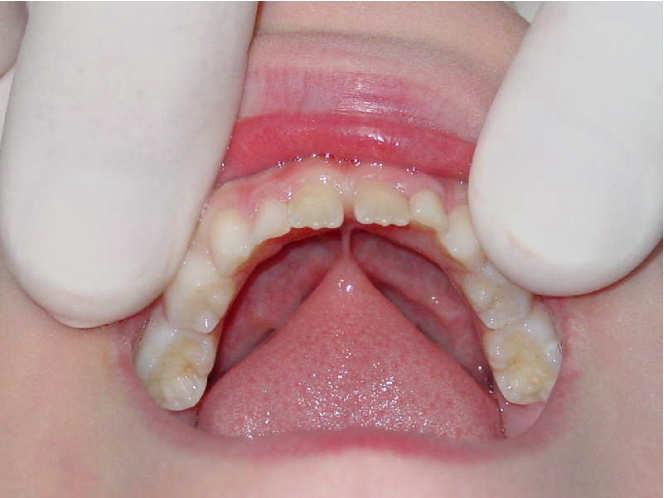

Diode Laser 810nm

Power: 2.5 Watt,

Pulsed 50 Hz ,Fibre 400 micron

2

Dott. Stefania Cristalli